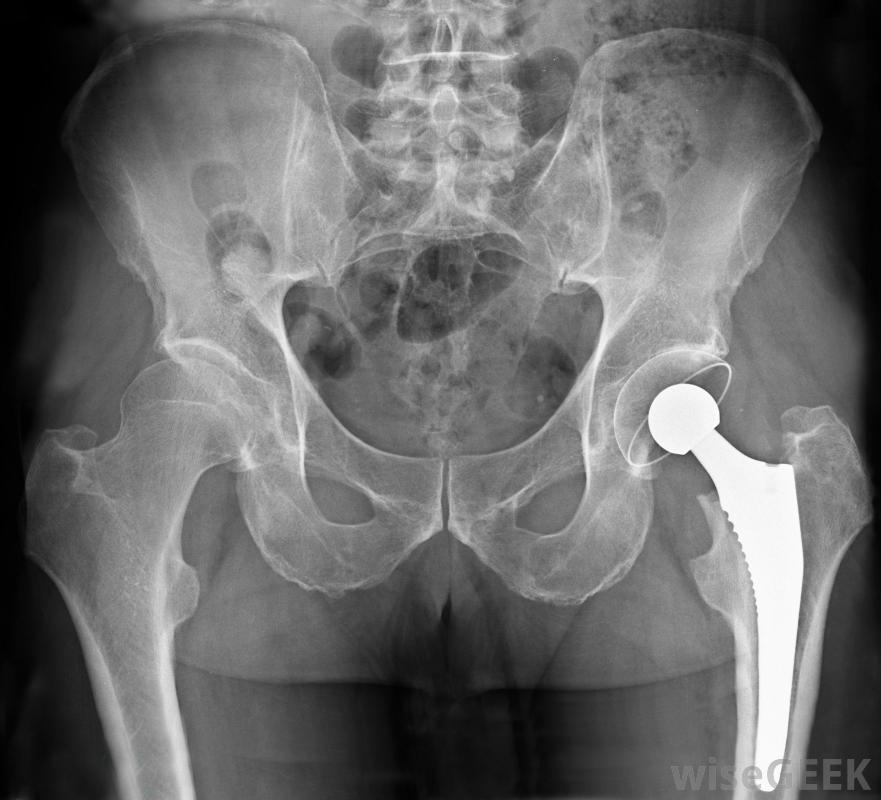

骨盆区域的X光片,显示一个金属置换髋关节一种叫做菌血症或败血症,也叫血液中毒,可以在关节置换术后的术后时期发生,菌血症和其他感染的发生率已经大大降低,除了预防菌血症外,在关节置换手术前使用抗生素通常可以预防术后关节感染